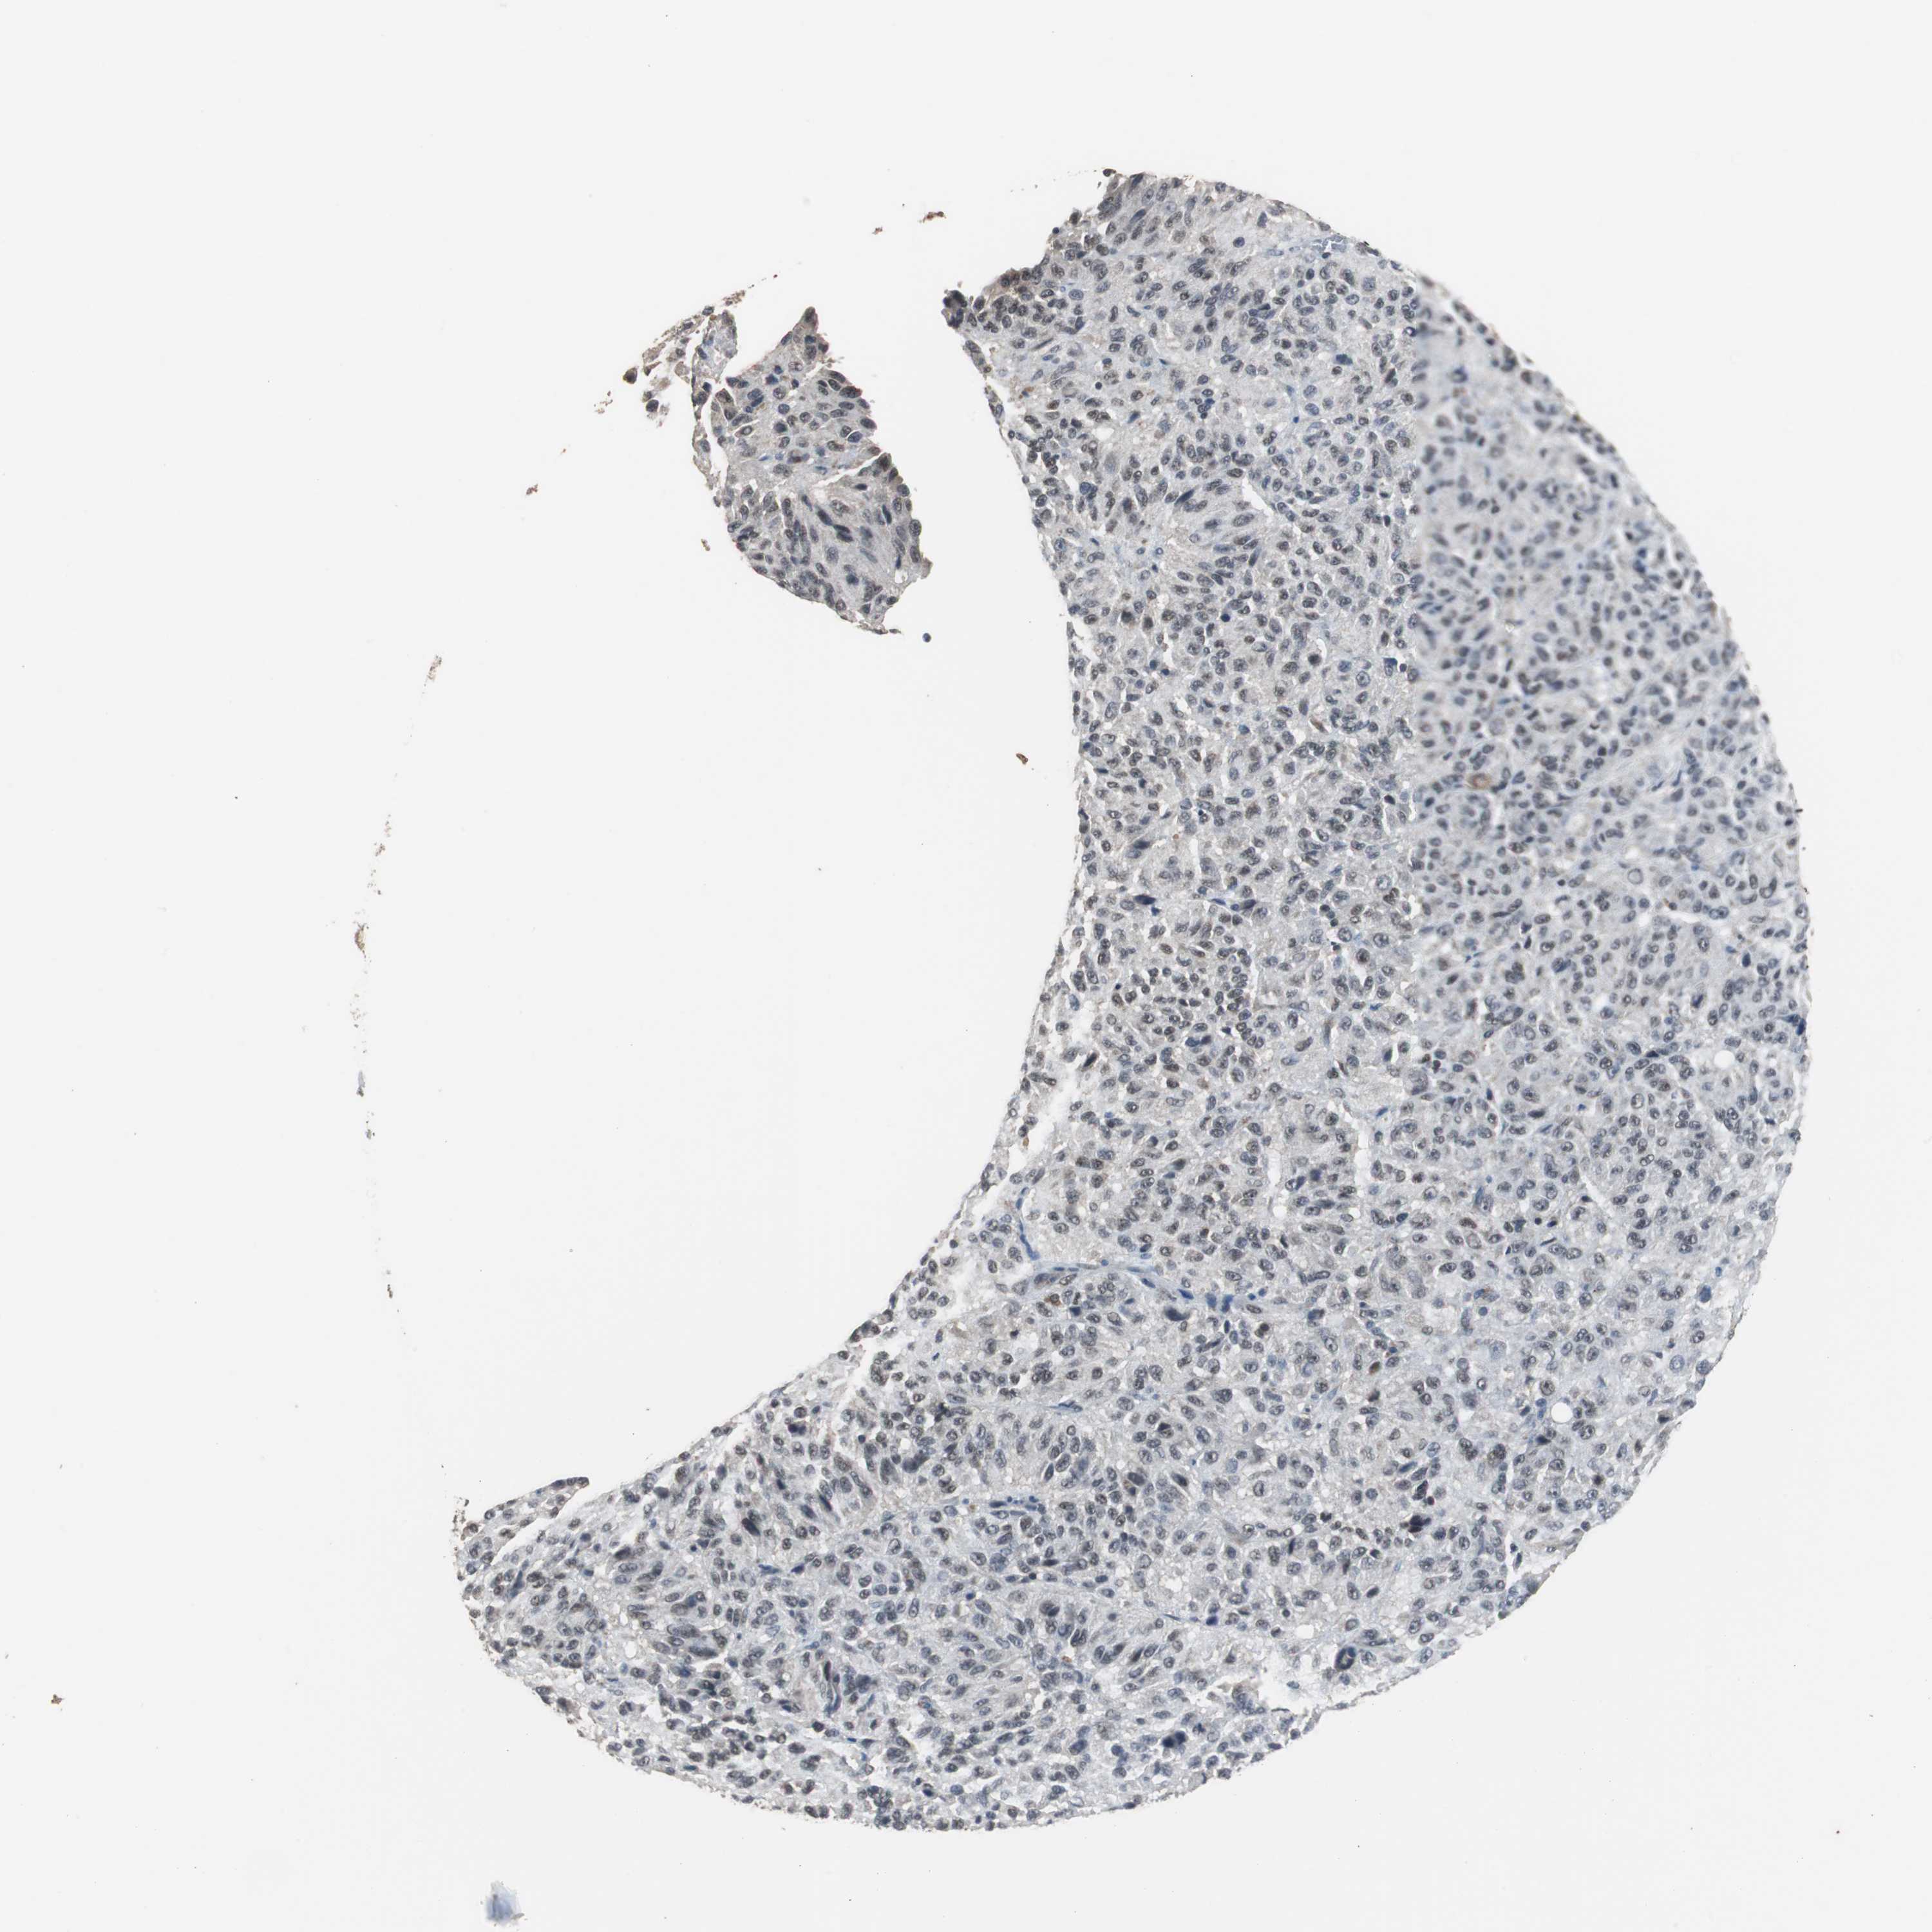

MELANOMA - Protein expressioni

A mouse-over function shows sample information and annotation data. Click on an image to view it in a full screen mode. Samples can be filtered based on level of antibody staining by selecting one or several of the following categories: high, medium, low and not detected. The assay and annotation is described here.

Note that samples used for immunohistochemistry by the Human Protein Atlas do not correspond to samples in the TCGA dataset.

Antibody stainingi

Antibody staining in the annotated cell types in the current human tissue is reported as not detected, low, medium, or high, based on conventional immunohistochemistry profiling in selected tissues. This score is based on the combination of the staining intensity and fraction of stained cells.

Each image is clickable and will lead to virtual microscopy that enables deeper exploration of all samples and also displays staining intensity scores, fraction scores and subcellular localization as well as patient and tissue information for each sample.

Antibody HPA006769

Antibody HPA006996

Staining

High

Medium

Low

Not detected

Intensity

Strong

Moderate

Weak

Negative

Quantity

>75%

75%-25%

<25%

None

Location

Nuclear

Cytoplasmic/membranous

Cytoplasmic/membranous,nuclear

Malignant melanoma, NOS

Malignant melanoma, Metastatic site